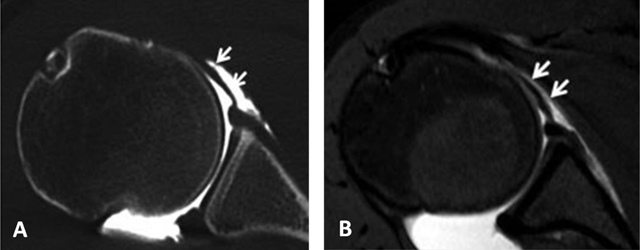

Figure 24

Pulley system. Axial fat-saturated T1-weighted MR arthrographic section at the level of the bicipital groove shows the biceps pulley (large arrow), formed by the fusion of the coracohumeral ligament, the superior glenohumeral ligament (thin arrow) and the transverse humeral ligament. The long head of the biceps tendon is pointed out by an arrowhead.